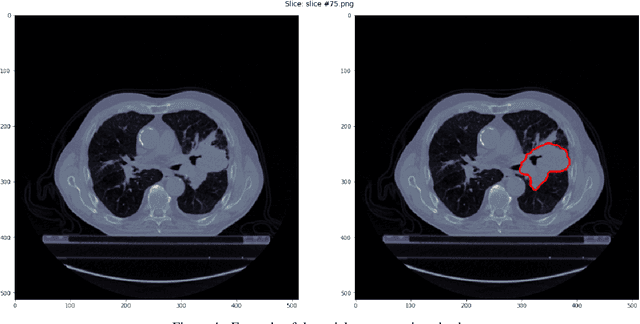

Abstract:Colorectal liver metastases (CRLM) are a major cause of cancer-related mortality, and reliable detection on CT remains challenging in multi-centre settings. We developed a foundation model-based AI pipeline for patient-level classification and lesion-level detection of CRLM on contrast-enhanced CT, integrating uncertainty quantification and explainability. CT data from the EuCanImage consortium (n=2437) and an external TCIA cohort (n=197) were used. Among several pretrained models, UMedPT achieved the best performance and was fine-tuned with an MLP head for classification and an FCOS-based head for lesion detection. The classification model achieved an AUC of 0.90 and a sensitivity of 0.82 on the combined test set, with a sensitivity of 0.85 on the external cohort. Excluding the most uncertain 20 percent of cases improved AUC to 0.91 and balanced accuracy to 0.86. Decision curve analysis showed clinical benefit for threshold probabilities between 0.30 and 0.40. The detection model identified 69.1 percent of lesions overall, increasing from 30 percent to 98 percent across lesion size quartiles. Grad-CAM highlighted lesion-corresponding regions in high-confidence cases. These results demonstrate that foundation model-based pipelines can support robust and interpretable CRLM detection and classification across heterogeneous CT data.